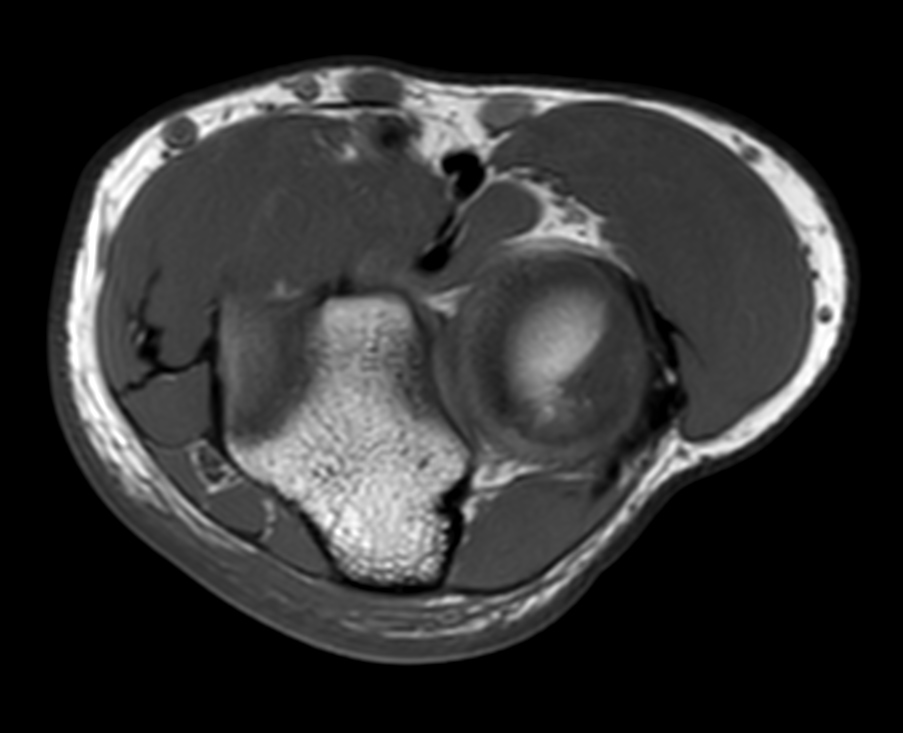

High quality Elbow imaging with Compressed SENSE

Spital Uster, Switzerland